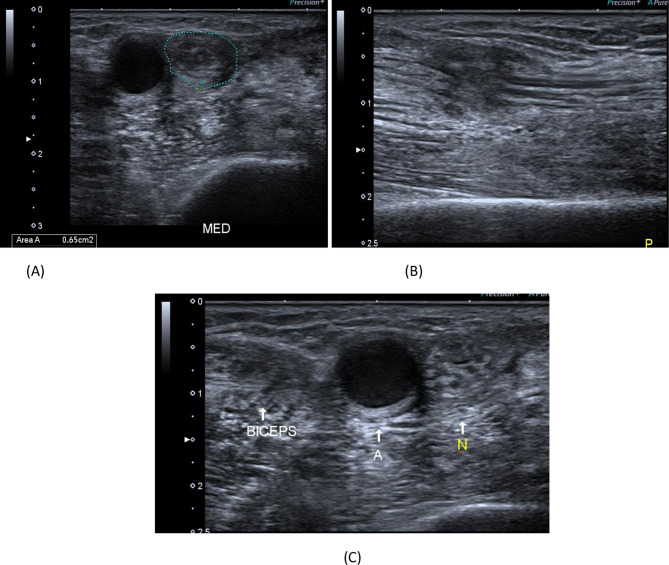

A 40-year- old male patient presenting with history of cut wound of the right arm just proximal to the elbow crease since September 2021. He gave history of operative repair of brachial artery injury. A B-mode image, transverse axis, shows abnormal architecture of the right median nerve at the distal arm with loss of the normal honeycomb appearance and related hypoechoic scar tissue formation. B B-mode image, longitudinal axis, shows discontinuous right median nerve at the distal arm with related hypoechoic scar tissue formation. C B-mode image, transverse axis, shows abnormal architecture of the right median nerve(N) at the distal arm with loss of the normal honeycomb appearance and related hypoechoic scar tissue formation, aneurysmal dilatation of the brachial artery (A) and distorted biceps muscle (BICEPS)